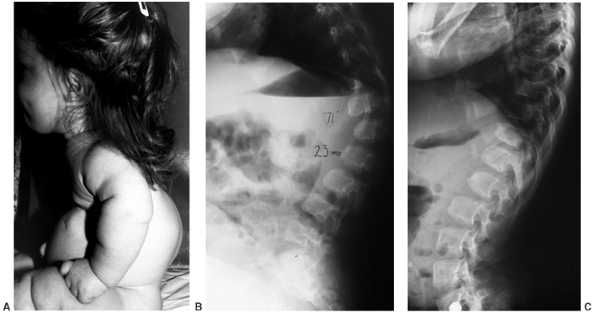

presumably because of low muscle tone, ligamentous laxity, and a large

cranium. The kyphosis is noncongenital and is centered at the twelfth

thoracic or first lumbar vertebra. These vertebrae become wedge shaped

anteriorly, although this is a reversible phenomenon (Fig. 8.8). Most patients improve by the second or third year of life after walking begins and muscle strength increases (11,21,50,51). However, in 10% to 15% of patients, kyphosis remains (Fig. 8.9),

and can increase the risk of symptomatic stenosis through pressure on

the conus, as well as through the secondary lumbar lordosis that it

induces. Therefore, treatment may be indicated at several phases of

![]() |

|

Figure 8.8 Thoracolumbar kyphosis in a 23-month-old achondroplastic child who has not walked yet. A: It is most pronounced in the sitting position. B: Radiograph shows hypoplasia of L1, with rounding-off of the anterior vertebral body corners. C: At 5 years of age, after a period of brace treatment, the shape of L1, as well as the overall kyphosis, has improved.